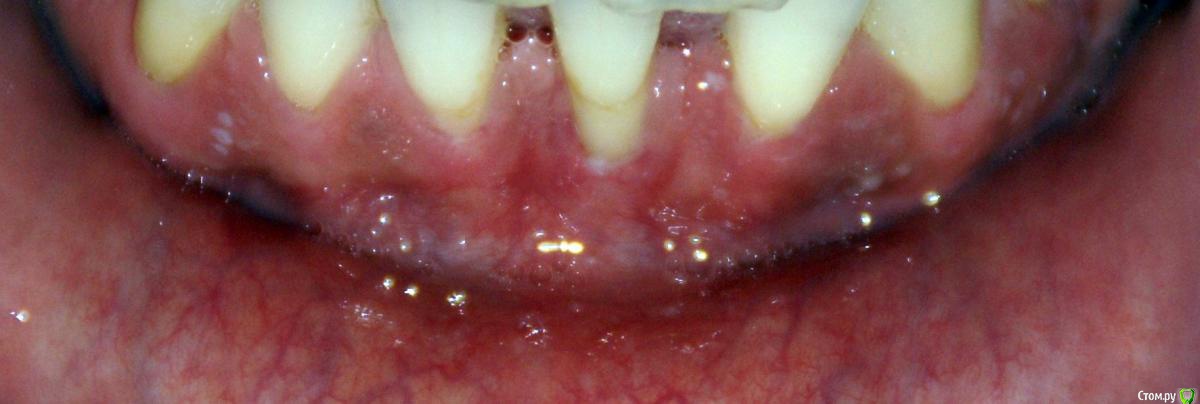

Irina_S Опубликовано 15 июня, 2017 Поделиться Опубликовано 15 июня, 2017 Здравствуйте, уважаемые специалисты! Заранее прошу прощения за не слишком качественные фото! Почти восемь месяцев назад мне была сделана вестибулопластика на нижней челюсти.За пять дней до операции ситуация во рту выглядела так: Для проведения операции были такие показания: Вот ещё описание самой операции, которая была 24 октября 2016 г.: Через шесть дней после операции: Ещё через шесть дней, 5 ноября: Прошла ещё неделя, 12 ноября: Следующий раз фото, к сожалению делалось через три с лишним недели, 4 декабря, в разных ракурсах: После этого визуальные изменения касались только уменьшения белёсых мест от разреза.Вот состояние на 10 июня этого года с разными вариантами оттягивания губы: По результатам заживления я не вижу разницы в глубине преддверия, ради чего и проводилась операция.К тому же всё время с момента операции присутствуют стягивающие ощущения и ощущение инородного тела в подбородке. Ответьте, пожалуйста, правильно ли была сделана операция вестибулопластики?Спасибо за внимание! Ссылка на комментарий